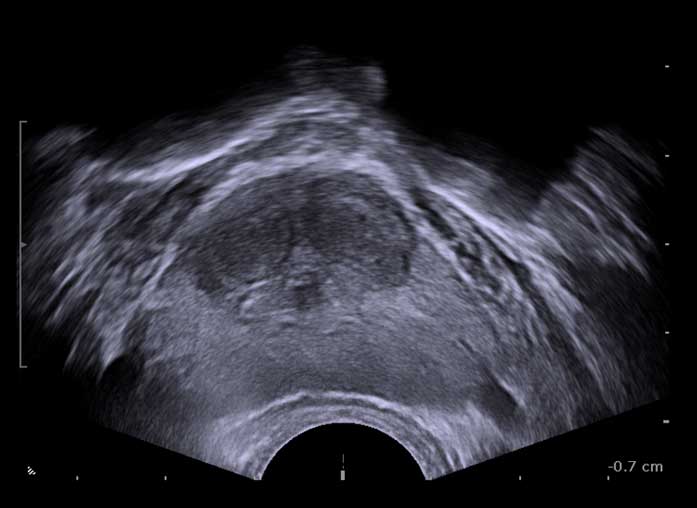

진료실에서 실제로 초음파 영상을 제시하면 환자들도 “가운데 막힌 게 보인다”라며 바로 이해한다. 특히 가운데에 잠자리 눈처럼 동그랗게 알맹이가 보이고 이행대가 바깥과 확연히 구분돼 보이면, 소변 길이 막혀 있을 가능성이 높다. 그래서 크기가 작아도 소변을 약하게 보는 환자가 있고, 반대로 크기가 크더라도 의외로 소변을 잘 보는 차이가 생긴다.

결국 중요한 건 크기보다 어떤 모양으로 요도를 막고 있는지 여부다.